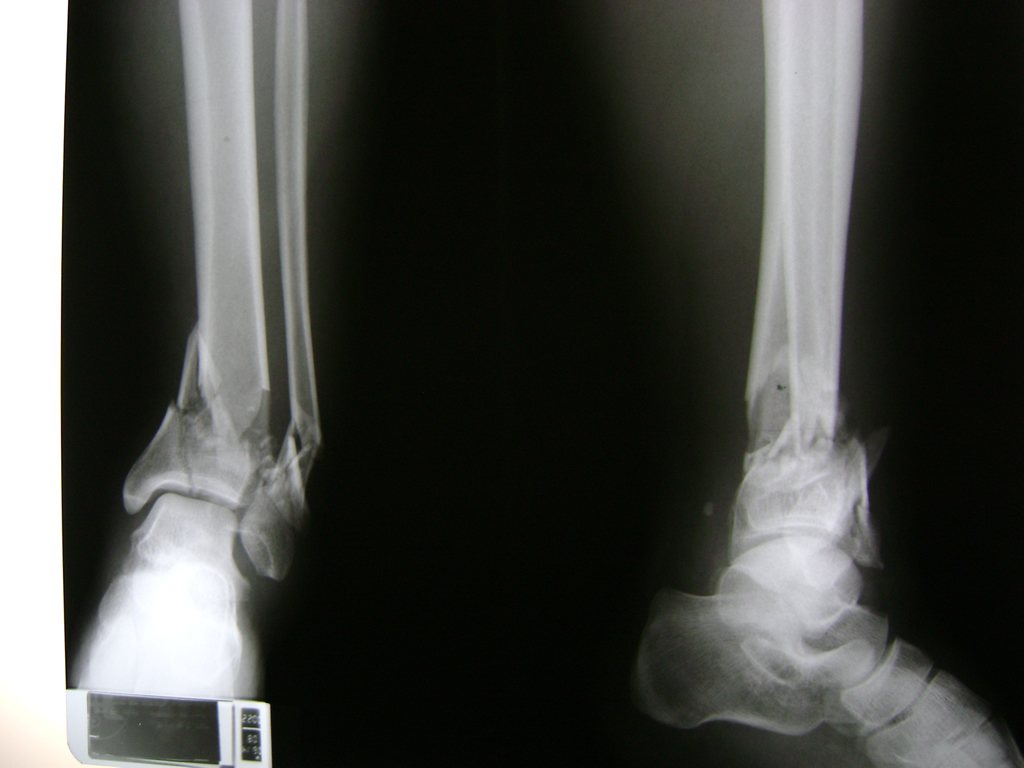

Una fractura de tobillo es la rotura de uno o más de los huesos del tobillo. Estas fracturas pueden ser:

Algunas fracturas de tobillo pueden requerir cirugía si:

- Los extremos de los huesos están desalineados entre sí (desplazados).

- La fractura se extiende hasta la articulación del tobillo (fractura intra-articular).

- Los tendones o ligamentos (tejidos que sujetan los músculos y los huesos entre sí) están rotos.

Cuando se necesita cirugía, es probable que esta implique el uso de clavijas de metal, tornillos o placas para sostener los huesos en su lugar mientras la fractura se consolida. Los elementos de soporte pueden ser temporales o permanentes.